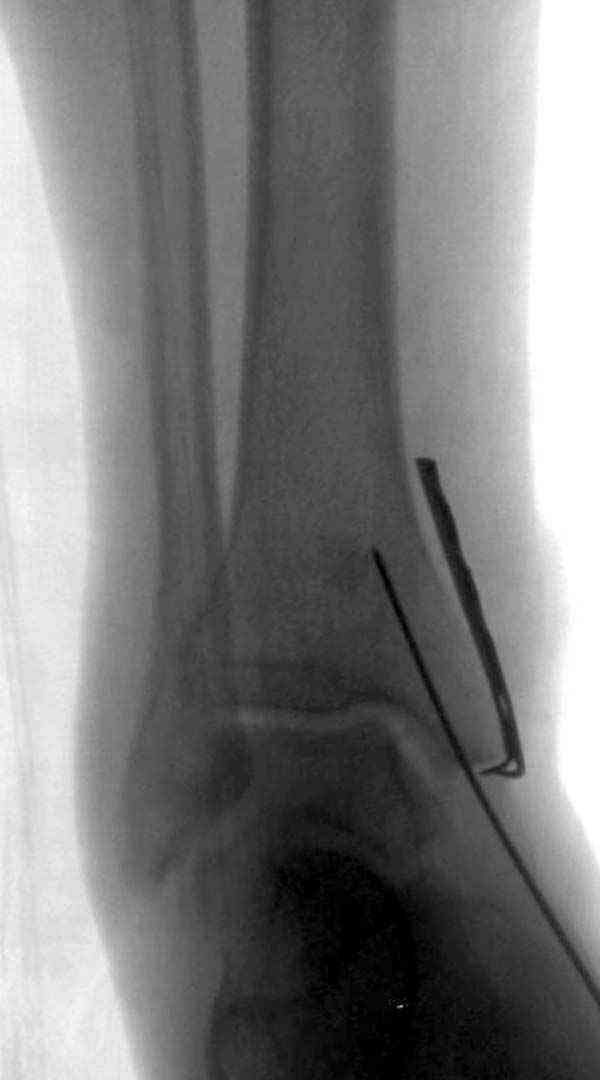

Достаточно быстрое восстановление функции.В октябре 2009г-почувствовала боль,в области рубца над гайкой открылся свищ.На Р-граммах-консолидация переломов и смещение гайки по стяжке.10.11.2009г-конструкции удалены,санация,заживление ран.В настоящее время пациентку ничего не беспокоит.На операции-раскручивание гайки-болталась на конце стяжки.Вопросы:какой механизм раскручивания и что я неправильно сделал?Свои версии:1)в области синдесмоза успела образоваться рубцовая ткань,которая при движении в суставе"пружинила",поскольку голеностопный сустав является спиральным, то и биомеханика подобна кривошипному механизму.2)Реконструктивная пластина не "реконструировалась" по форме лодыжки.Наложил,как есть.То есть подпружинивала сама пластина.Ну,это мои догадки.Что нужно,чтобы избегать впредь таких,пусть и не "страшных"осложнений:Рассверливать через лодыжку область синдесмоза?Ставить шайбу-гровер?Тщательно моделировать пластину?Прилагаю сравнительные снимки-сразу после операции и перед удалением конструкции.

Раз ,есть желание посмотреть другую проекцию выкладываю-ну лучшего качества нет...

Кликните для загрузки файла DSC05256.JPG